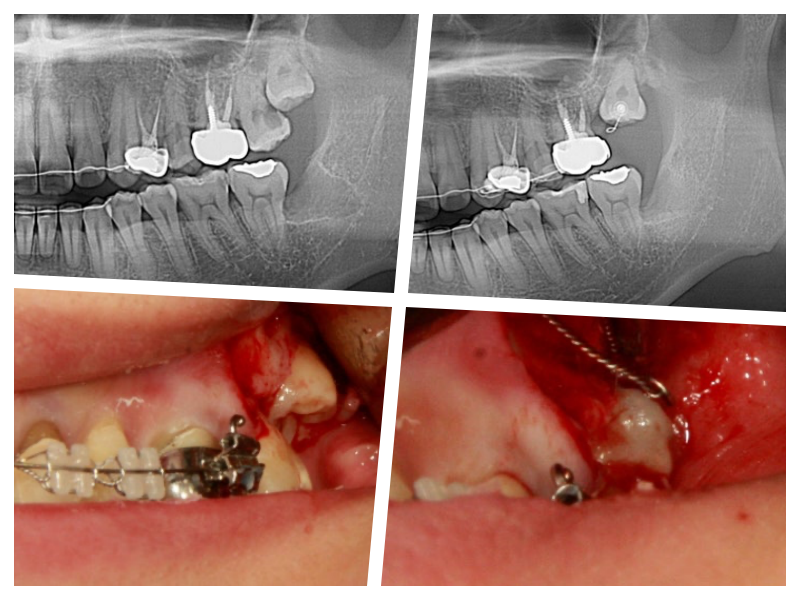

Case details

사랑니의 쓸모를 찾아서~

사랑니 교정

사랑니를 교정치료를 통해 어금니로 사용하는 케이스